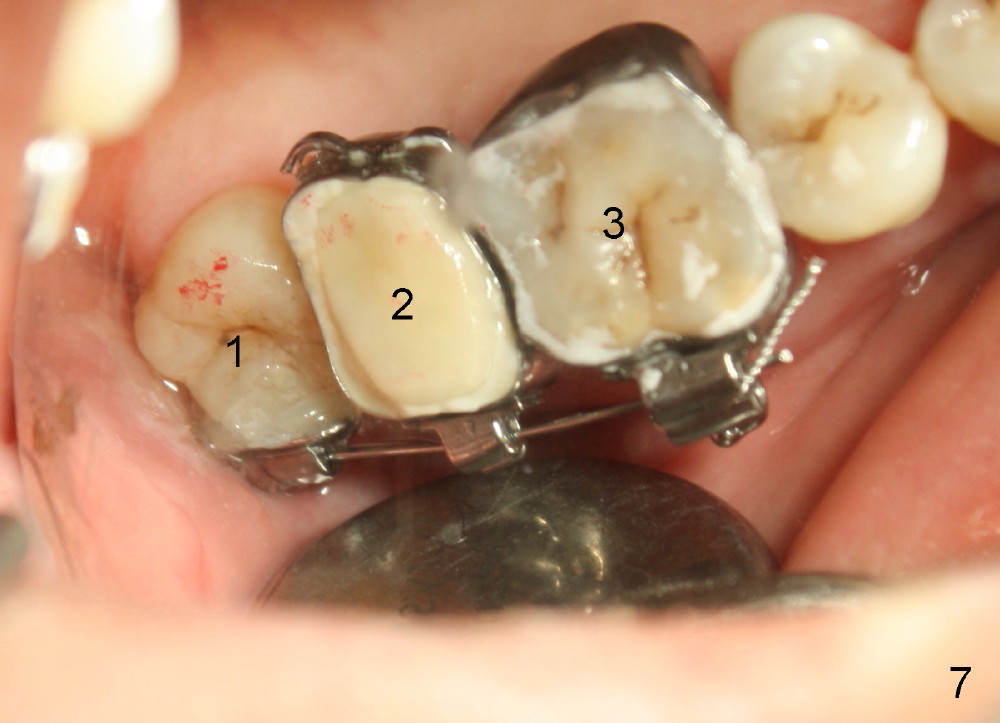

A 48-year-old lady is a dental phobic and has generalized chronic periodontitis. Bone loss around the tooth #2 has been severe for the last 5 years (Fig.1,2 *). Finally she agrees to have #2 (symptomatic) extracted and immediate implant placed (Fig.3 I). A 7x17 mm implant has to be used to achieve primary stability. The remaining buccal and lingual gaps are filled with allograft and membrane (Fig.4 *). Fig.5 shows that there is a space between the tooth #1 (asymptomatic) and the immediate implant (I). The wound/socket is protected by applying perio dressing around an abutment (Fig.6 A). Postop the patient is pain free; the perio dressing dislodges by itself. She returns 3.5 months later for restoration; but the tooth #1 has shifted mesially (Fig.6 arrow). The patient is not so willing to have #1 removed. Bands and bracket are placed in the neighboring teeth including a provisional crown to move the shifted tooth (with mobility) distally (Fig.7,9). The 2nd reason for #1 shifting is abnormal occlsual scheme on the right posterior region (Fig.8); mobility of #1 is the 1st one. The 3rd one is probably bruxism. In 5-6 weeks, the tooth #1 has moved to a desirable position (Fig.10, as compared to Fig.3,5). There is enough space for restoration (Fig.11,12).

In all, posterior immediate provisional should have normal proximal contact so that the neighboring periodontally affected teeth do not shift while the implant is osteointegrating. In order to avoid fibrointegration, the occlusal contact should be off. The patient requests an immediate provisional for the next implant. The same restoration will be fabricated for an implant at a healed site.